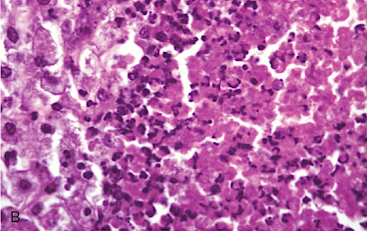

Name the type of necrosis that is present on the histological slide below:

caseous necrosis